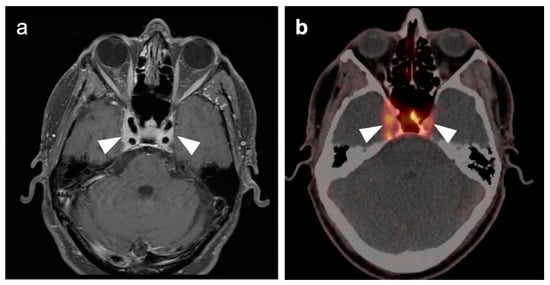

2.3. Nasopharyngeal Carcinoma